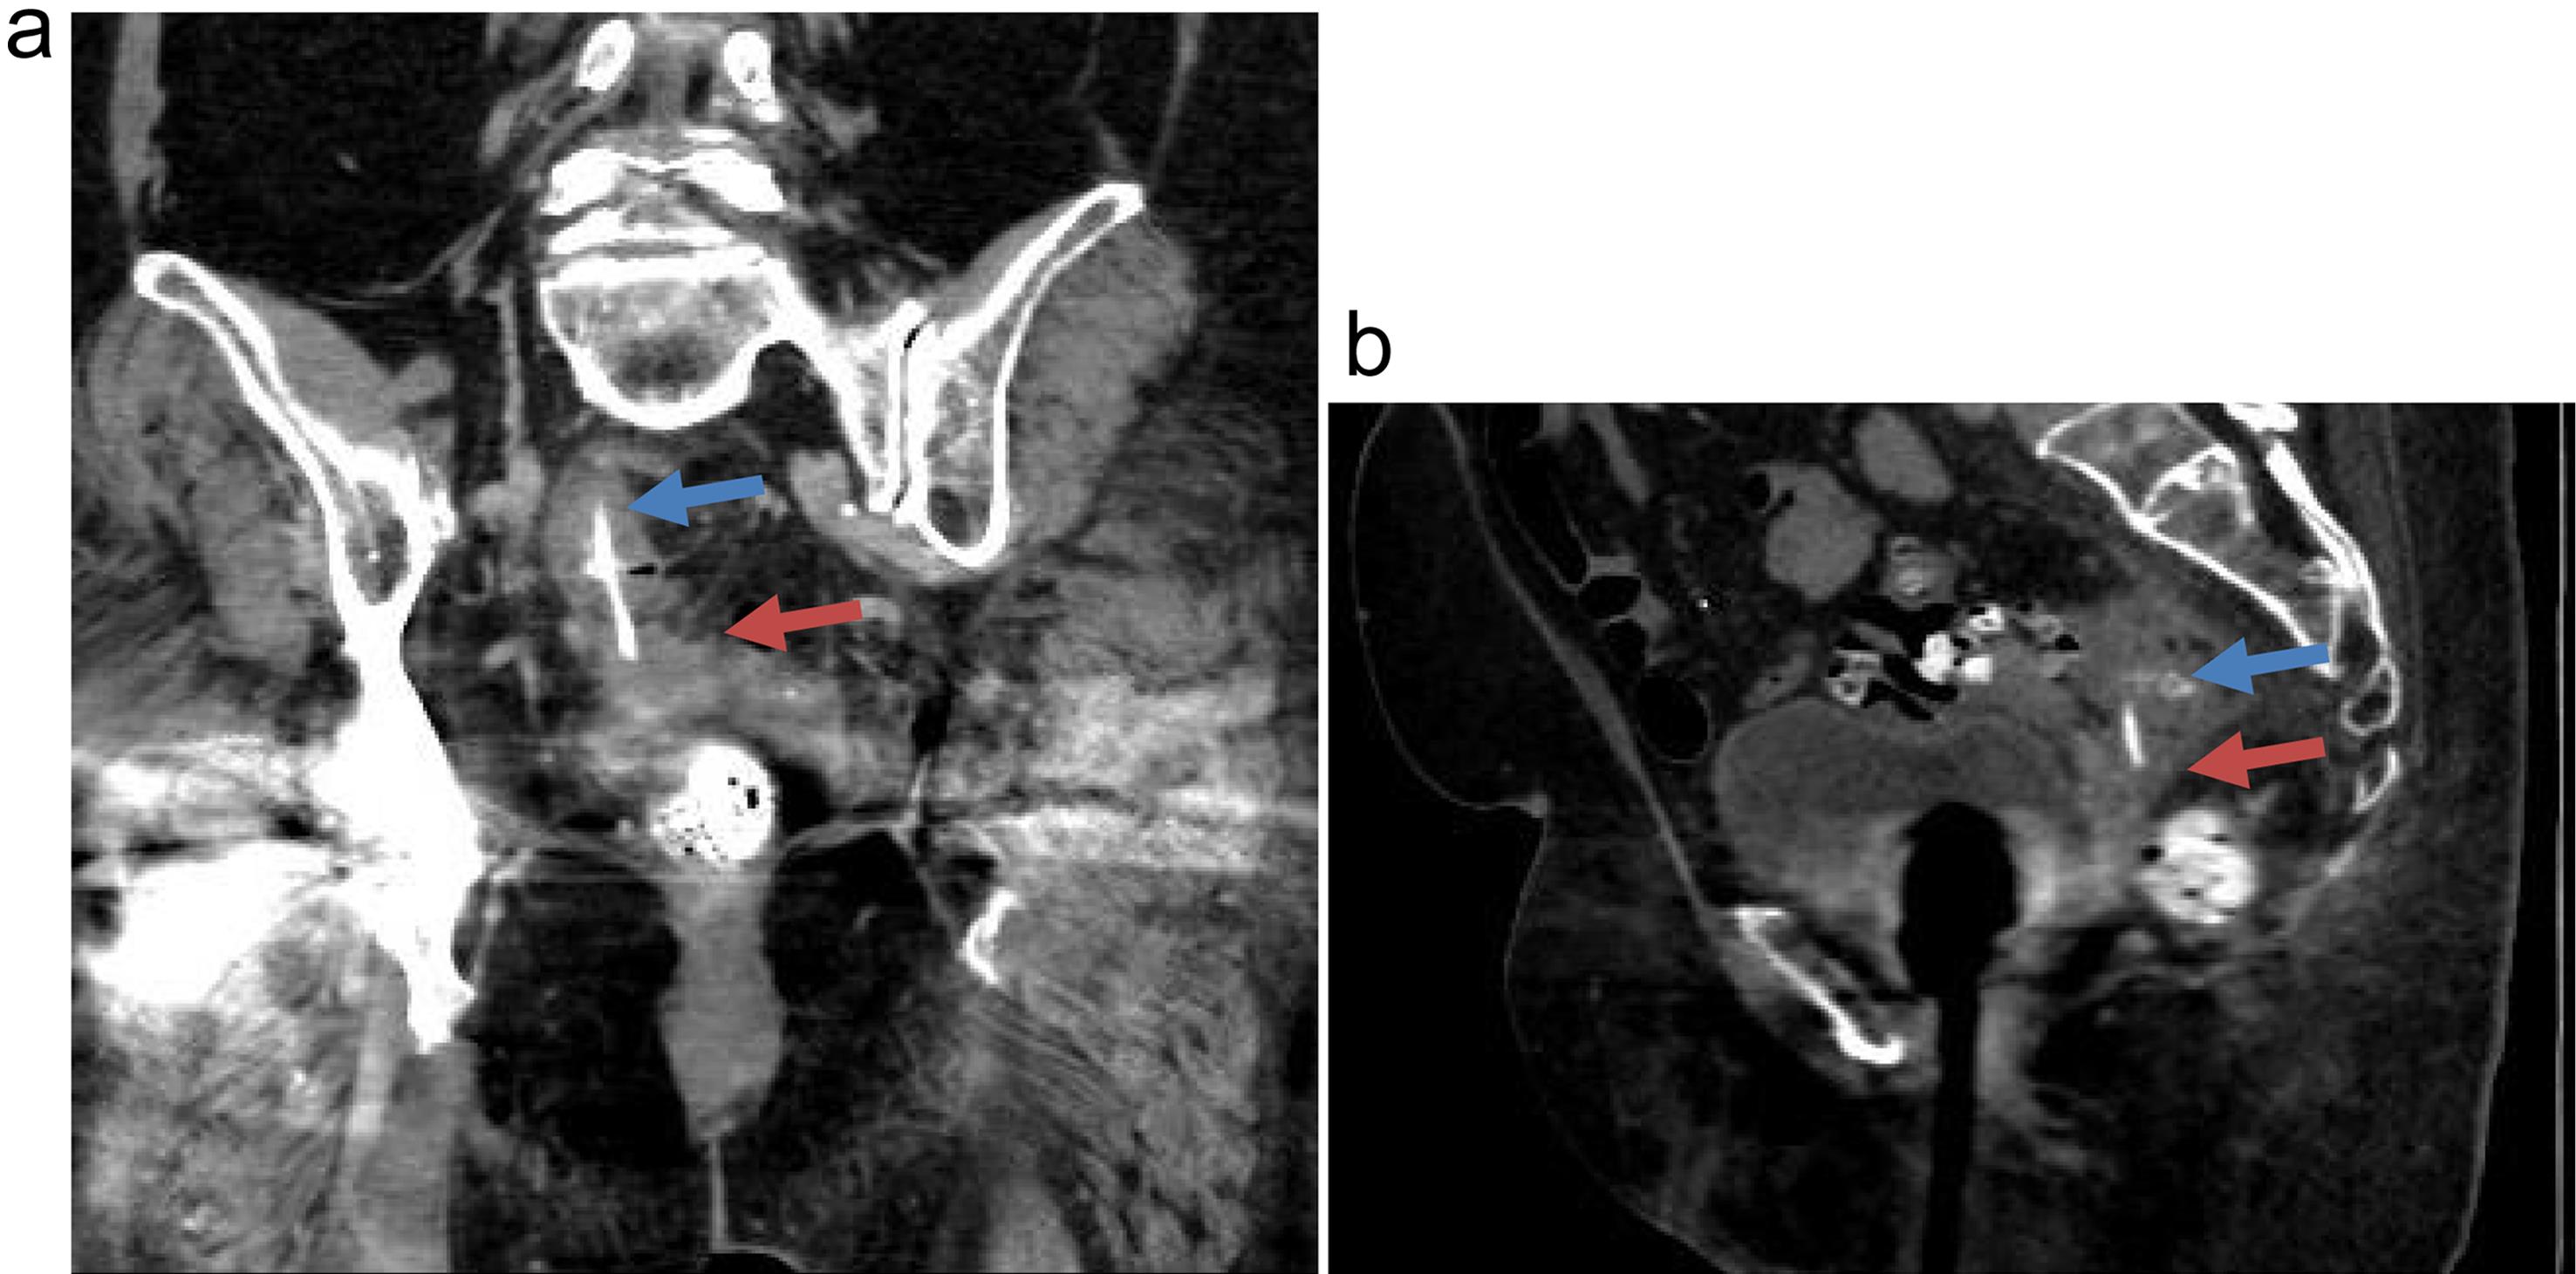

An 85-year-old woman presented with a two-week history of intermittent left lower quadrant pain and diarrhea. The pain progressively increased in severity and frequency and radiated to the rectum. She had been seen at another hospital emergency department, where a CT scan of the abdomen and pelvis revealed a 3.9 cm radiopaque linear density within the sigmoid colon, suggesting a foreign body. She was discharged home without intervention, with a recommendation for a follow-up reimaging CT scan of the abdomen on an outpatient basis. Her past medical history included diverticulosis coli, gastroesophageal reflux disease, irritable bowel syndrome, dementia, hypertension, hyperlipidemia, rheumatoid arthritis, and cerebrovascular disease. Six days later, she was seen by her physician with continued abdominal pain radiating to the rectum and diarrhea and was then referred immediately to the hospital emergency department. Physical examination revealed left lower quadrant abdominal tenderness without guarding or rebound tenderness. Laboratory tests, including CBC (complete blood count) and complete metabolic panel, were unremarkable. A CT scan of the abdomen and pelvis with IV contrast revealed a 3.7 cm slightly obliquely vertically oriented tubular radiopaque structure centered within the sigmoid colon lumen, suggestive of a foreign body. The cephalad tip of the presumed foreign body appeared within the lumen or wall of the mid-sigmoid colon. The caudal tip appeared to extend beyond the sigmoid colon wall, through the adjacent mesenteric fat, with the tip appearing within the lower uterine segment, possibly within a diverticulum. The uterus was otherwise unremarkable. There was mild wall thickening of the sigmoid segment, with adjacent fluid and small, likely reactive lymph nodes. There was no pneumoperitoneum appreciated (Fig. 1).

CT scan images.

Fig. 1  CT scan images.

Coronal (a) and sagittal (b) CT images of the pelvis show a vertically oriented radiopaque foreign body within the sigmoid colon. The proximal tip of the foreign body is positioned within the sigmoid colon lumen (blue arrow), and the distal tip is within the uterus (red arrow). The foreign body traverses a thin band of intersecting pelvic fat.